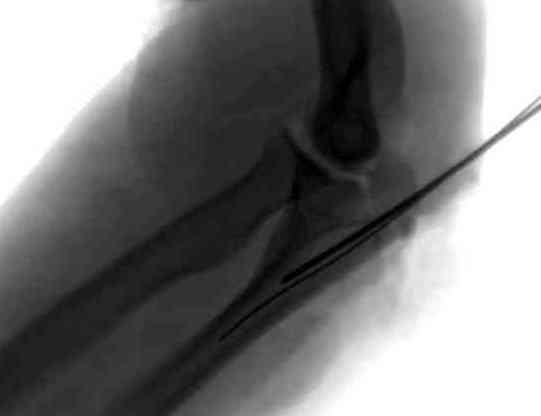

При лечении переломов локтевого отростка положение

больного на операционном столе подсказывается наличием дополнительных переломов, например при переломах таза или ацетабулум предпочтительное положение на спине.

При отсутствии других переломов мы предпочитаем

положение больного на боку, рука на подставке, согнутая в локтевом суставе. Удобно для операторов и легко для рентгенологического контроля.

Для доступа к венечному отростку, при наличии перелома локтевого отростка не обязательно проведение дополнительной остеотомии медиального надмышелка.

Обычный стандартный доступ позволяет провести полную ревизию сустава, через фрагменты отломков открывается доступ к венечному отростку и имеется возможность репозиции с окончательной фиксацией. В книге “AO Principles of Fracture Management” описаны методика и варианты фиксации.